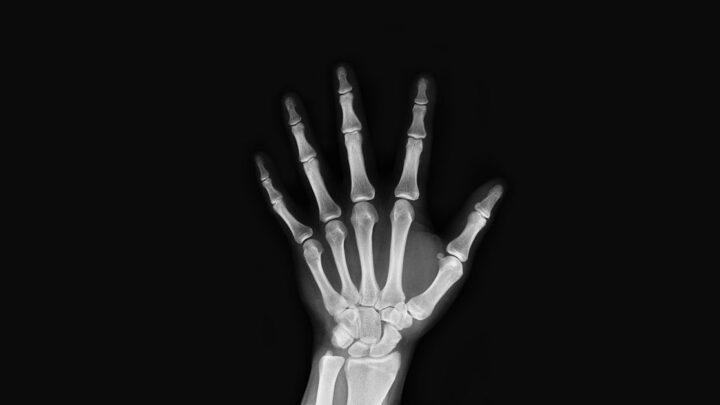

Ultrassonografia

Ultrassonografia Pélvica

Se você passou por períodos dolorosos, sangramento vaginal incomum, dor pélvica crônica ou dificuldade em engravidar, pode recomendar uma ultrassonografia…